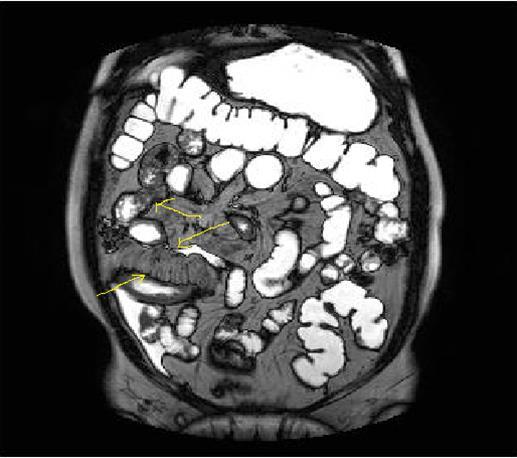

Bowel wall thickening with increased luminal and extra-luminal signal changes on FS images, showing active inflammation, edema in the adjacent intraperitoneal and mesenteric spaces, active inflammation; bowel wall thickening and enhancement on post-contrast T1W images plus high signal intensity on T2W- FS images7, 9, 12, 14, 17, 18, 19, 20, 21 (Figure 4a-b).

Chronic disease without active inflammation; Bowel wall thickening and enhancement on postgadolinium T1W images plus low signal intensity on T2W-FS images with possible stenosis and obstruction due to fibrosis, chronic disease with active inflammatoryexacerbations;these conditions can overlap with active inflammation, require longitudinal repeated scanning7, 12, 14, 20,26, 27, 28, 29, 30 (Figure 5a-b, Figure 6a-b)

Figure 4a.Mucosal involvement and lack of opacified ileal segments with loss of intestinal folds and increased bowel wall thickness due to Crohn’s disease on T2W coronal sequence after OCA, presented at 37 years old male with moderate Crohn’s disease.

Figure 4b.Mucosal, luminal and bowel wall involvement in Crohn’s disease with skipped lesions, seen at T2W axial image after OCA, presented at 45 years old male with severe inflammatory disease.